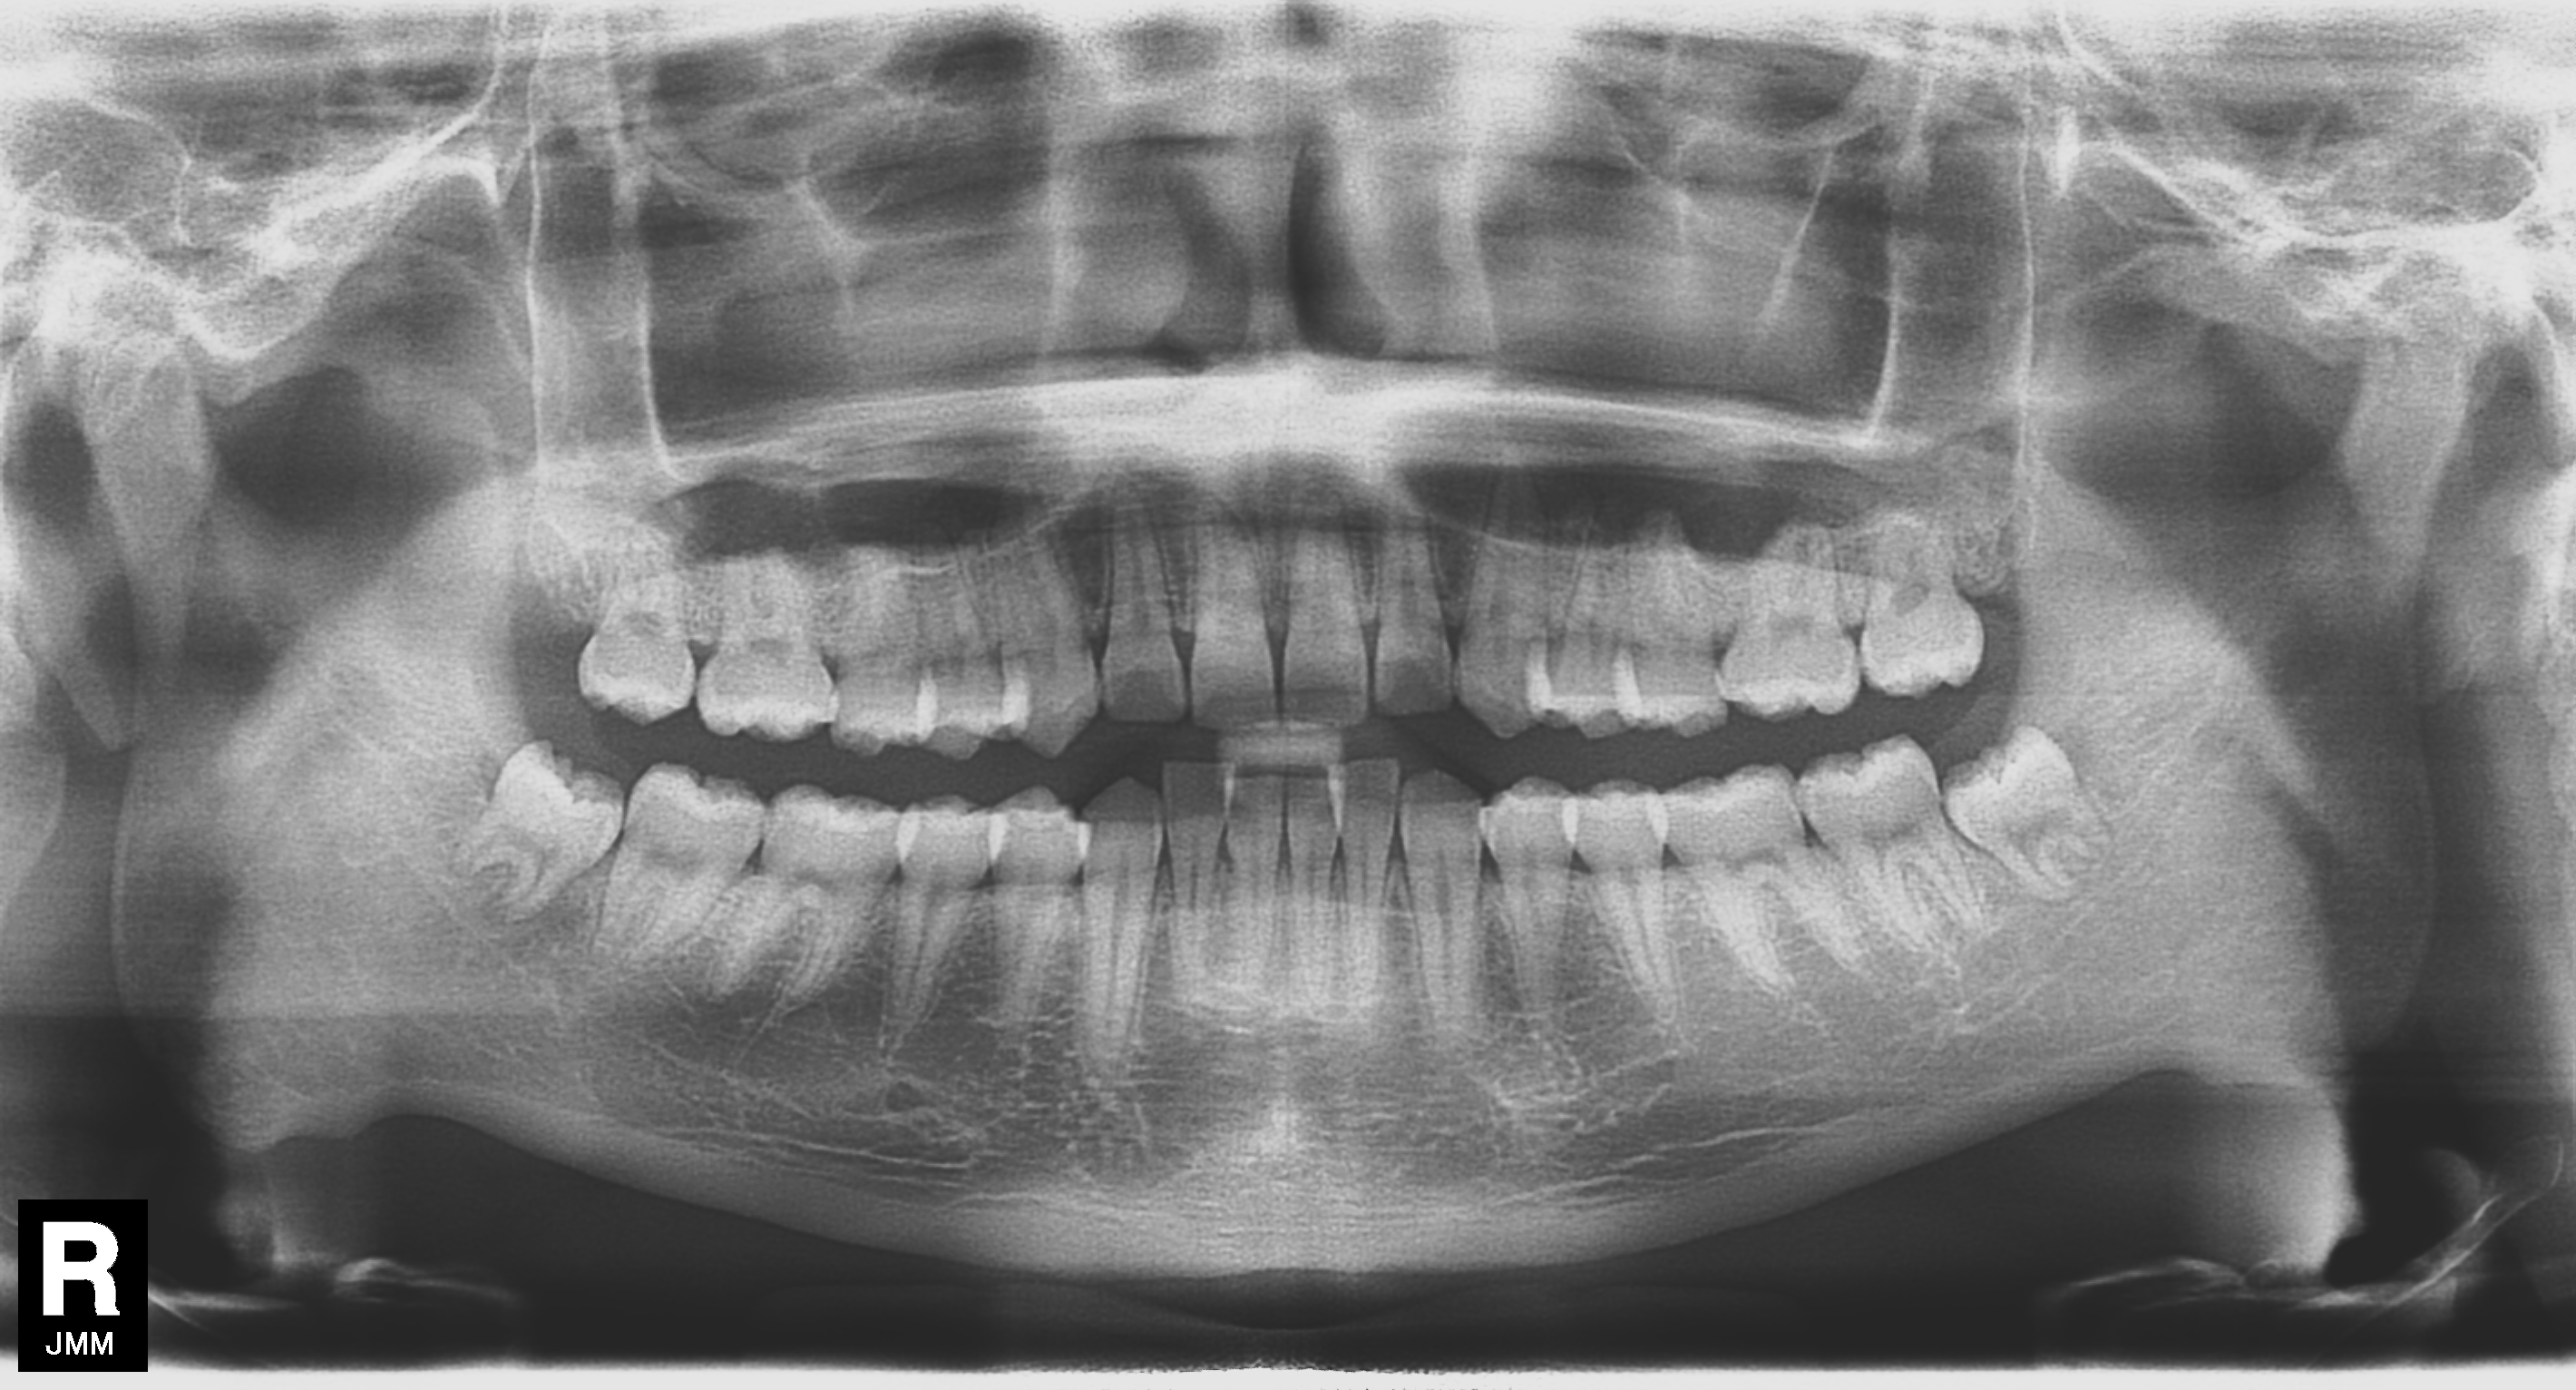

例えば、以下のレントゲンをご覧ください。歯周病になってしまっている患者様(左側写真・症状無し)と歯周病になっていない患者様(右側)の比較です。レントゲンを見れば状態がわかりますが、鏡で自分のお口を見るだけではなかなか気づくことができないのが歯周病です。

歯周病が進行している

進行していない